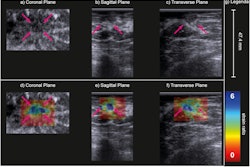

This is where sonography comes into play. Breast imagers have used various sonographics to categorize benign versus malignant lymph nodes. These include size, shape, and morphologic features of the nodes. However, the researchers noted that it is “extremely difficult” to differentiate between malignant and benign lymphadenopathy on imaging, with biopsy often needed to confirm findings.

Wadhwa and colleagues sought to assess morphologic features of axillary nodes on ultrasound in predicting malignancy. They also wanted to explore the incidence of malignancy in axillary nodes based on their imaging mode of detection.